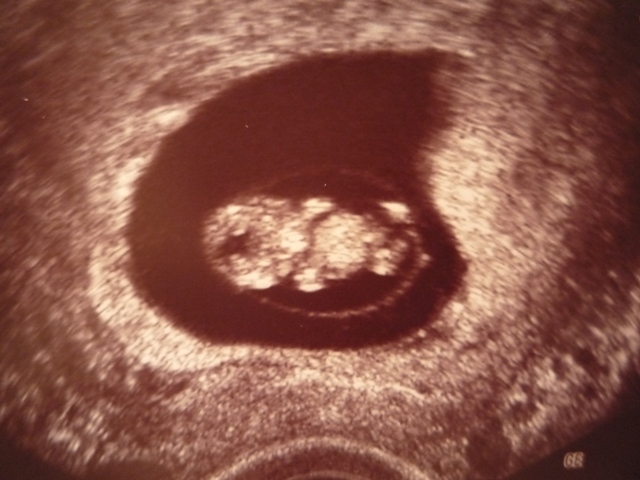

Melde mich auch noch kurz vorm Ins-Bett-gehen. Bei mir ist soweit alles o.k., ich hatte ja heute wieder US-Kontrolle und den beiden Bauchzwergen geht es sehr gut, strampeln fleissig. Ich hatte Recht mit meiner Vermutung und Zwilling A hat sich wieder gedreht, d.h. nun liegen wieder beide mit dem Kopf nach unten wobei sich Zwilling B leicht quer über Zwilling A schiebt. Die beiden sind fast gleich schwer und haben schon ein stolzes Gewicht von ca. 1740 gr. - also zusammen schon soviel wie ein "reifes" Baby - kein Wunder werde ich immer kurzatmiger. Sind beide ca. 40 cm gross. Gebärmutterhals immer noch bei guten 3.4 cm und Muttermund fest verschlossen. Einzig Zwilling A hat etwas weniger Fruchtwasser, aber nicht besorgniserregend. Muss aber kontrolliert werden und deshalb darf ich bereits in zwei Wochen wieder zum nächsten US.

@Wuschel: Schön konntest Du das Herzchen schlagen sehen - und bestimmt bist auch Du bald stolze Besitzerin eines Mutterpasses!